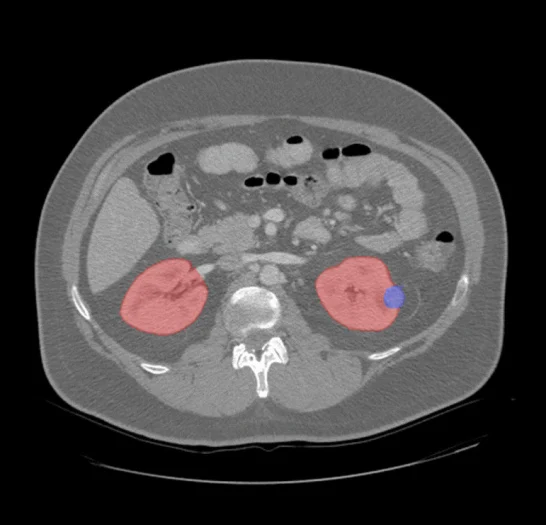

Renal CT Annotation & Segmentation

Pareidolia Systems offers high-precision renal CT annotation and segmentation services that enhance medical image analysis and fuel AI-driven nephrology solutions. Pareidolia’s domain experts deliver pixel-level segmentation of renal parenchyma, lesions, and vascular structures, ensuring accurate delineation of tumor margins, kidney stones, and vessel morphology. Using advanced annotation tools and standardized workflows, we produce clinically validated datasets that support diagnostic and research applications.